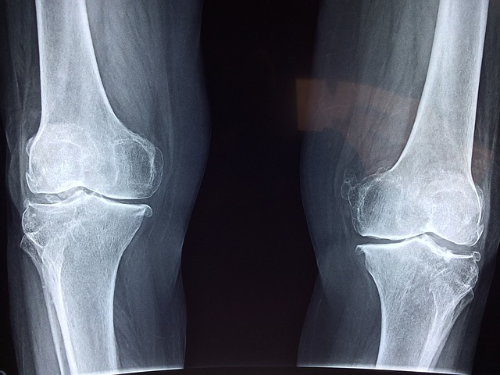

퇴행성 관절염은 나이가 들면서 발생하는 관절 질환으로, 통증, 염증, 연골 손상 등의 증상을 유발합니다. 콘로인 캡슐은 퇴행성 관절염 치료에 사용되는 일반의약품으로, 통증 완화와 연골 보호 효과를 통해 증상 개선에 도움을 줍니다.

콘로인 캡슐은 골관절염과 퇴행성 관절염 치료를 위한 일반의약품입니다. 이 약은 콘드로이친(콘드로이틴)이라는 성분을 함유하고 있어, 연골조직의 기초 구성을 변화시키는 효소인 leukocyte elastase의 작용을 억제하여 약효를 발휘합니다.

콘로인 캡슐은 연골조직의 기초 구성을 변화시키는 효소인 leukocyte elastase의 작용을 억제하는 효과가 있습니다. 이로써 경증에서 중등도의 골관절염(퇴행성관절염) 치료에 사용됩니다.